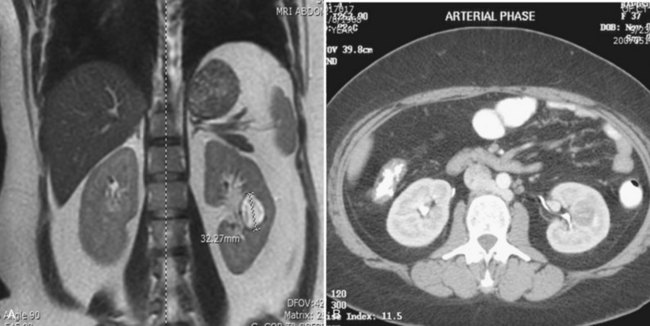

Tumor thrombus involving the IVC should be suspected in patients with lower extremity edema, varicocele, dilated superficial abdominal veins, proteinuria, pulmonary embolism, right atrial mass, or nonfunction of the involved kidney. MR venography is the authors’ preferred study for evaluating the presence and the distal extent of involvement of the IVC (Pritchett et al, 1987; Goldfarb et al, 1990) (Fig. 54–86). The use of invasive inferior vena cavography is limited to those patients with a nondiagnostic MR venogram or ultrasound evaluation, in those in whom MRI is contraindicated, and in patients who underwent preoperative angioinfarction with coils that would produce scatter leading to poor quality MR images (Fig. 54–87). Transesophageal echocardiography (Treiger et al, 1991; Glazer and Novick, 1997) and transabdominal Doppler ultrasonography (McGahan et al, 1993) are also useful. In patients with known IVC tumor thrombus the authors perform intraoperative transesophageal echocardiography to evaluate the distal extent of the tumor thrombus before making the incision.

Figure 54–86 A, Coronal MR image demonstrates tumor extending to the level of the diaphragm. B, Sagittal MR reconstruction demonstrates thrombus that extends farther into the right atrium. The patient would eventually require cardiopulmonary bypass and deep hypothermic circulatory arrest.

Before partial nephrectomy, evaluation of patients with renal cortical tumors should include imaging to identify locally extensive or metastatic disease. Preoperative imaging should also delineate relevant regional anatomy, intrarenal anatomy, and vasculature to minimize blood loss and damage to adjacent renal parenchyma. Invasive renal arteriography has largely been replaced by noninvasive 3D CT angiography, which offers excellent anatomic detail. 3D CT integrates information from arteriography, venography, excretory urography, and conventional two-dimensional CT into a single imaging modality (Fig. 54–130). In addition to tumor staging, 3D reconstructions of contrast-enhanced CT angiograms, MR images, or MR venograms are useful for planning site and extent of planned resection and to determine proximity to the renal hilum, intrarenal vasculature, and collecting system (Fig. 54–131). 3D CT accurately demonstrates involvement of the collecting system by tumor (Derweesh et al, 2003).

Figure 54–131 A, Contrast-enhanced CT scan demonstrating right renal mass. B, Three-dimensional reconstruction demonstrates a large intrarenal component to the mass. C, Arterial reconstruction shows lower pole renal artery in close proximity to the renal mass.